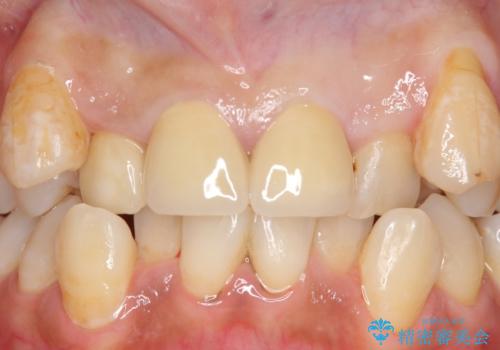

オールセラミッククラウン 長期間放置してきた前歯の虫歯治療

その後右上1,2番目及び左上1番目の歯に対してオールセラミッククラウンによる補綴を行いました。

今回用いたオールセラミッククラウンはジルコニアフレームという白い素材の上にセラミックを盛っているため、審美性が非常に高いのが特徴です。

また、ジルコニアは人工ダイヤモンドの材料にも使われているほど高い強度を持っており、そのためオールセラミッククラウンは審美性だけでなく、奥歯やブリッジの補綴も可能とするクラウンです。